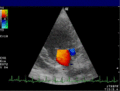

Bei der farbkodierten Doppler-Sonografie wird für einen großen Bereich eines konventionellen Ultraschallbildes (Color-Window) die örtliche Doppler-Frequenz (= mittlere Flussgeschwindigkeit) und deren Schwankungsbreite bestimmt. Damit möchte man die Turbulenz der Strömung abschätzen. Aufgrund der statistischen Bewegungen der Streuteilchen ist die Schwankungsbreite der Fließgeschwindigkeit jedoch stets größer als die Turbulenz. Das Ergebnis wird in Falschfarben auf dem B-Bild überlagert, also in Farbtönen von rot und blau für verschiedene Blutgeschwindigkeit und grün für Turbulenz. Hierbei steht üblicherweise die Farbe Rot für Bewegung auf den Schallkopf zu, während mit blauen Farbtönen Flüsse weg von der Sonde codiert werden. Bereiche der Geschwindigkeit 0 werden durch die Elektronik unterdrückt.

-

Anwendung des Doppler-Verfahrens bei einer Herzuntersuchung: Mitralklappeninsuffizienz